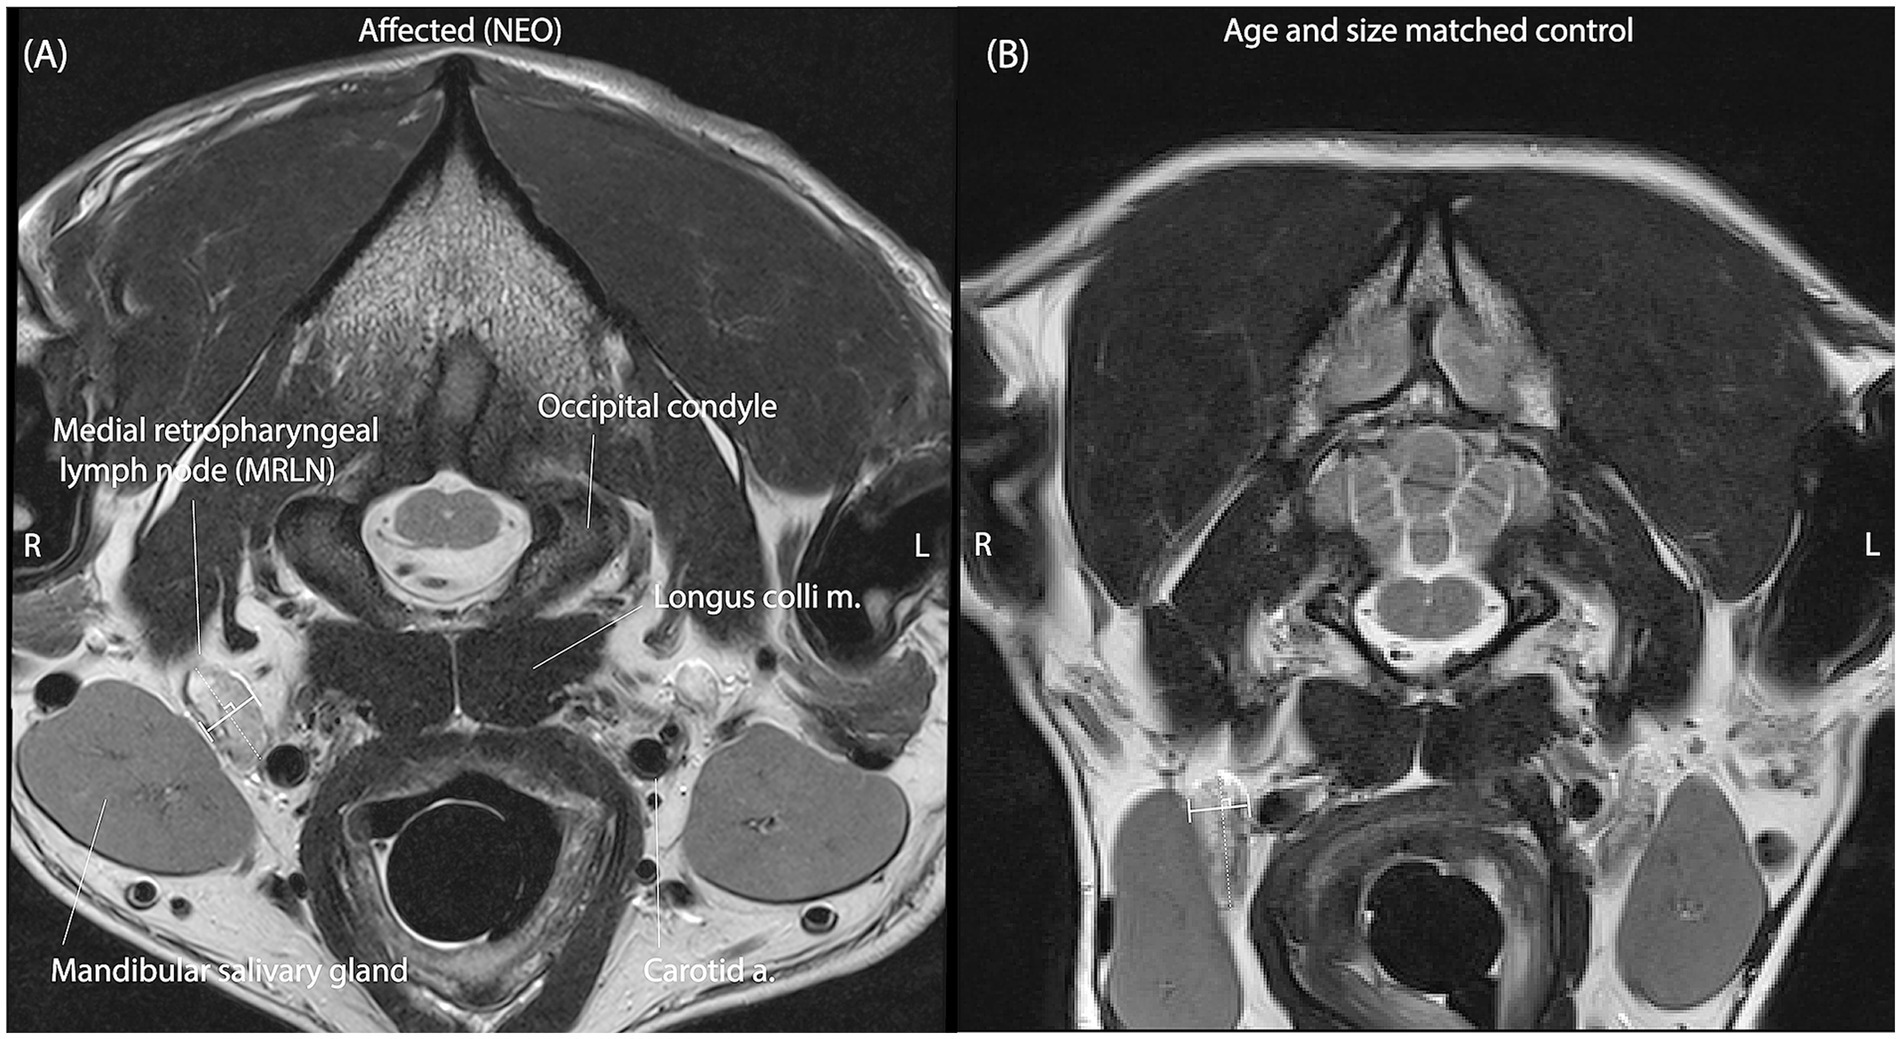

Introducción: El objetivo de este estudio es estimar los valores de referencia para los ganglios linfáticos retrofaríngeos mediales (MRLN) medidos en estudios de resonancia magnética de alto campo (3T) de la cabeza/cerebro canino utilizando imágenes de espín-eco T2 transversal y determinar si los perros con enfermedad cerebral estructural exhiben ganglios linfáticos retrofaríngeos mediales que son más grandes de lo esperado a partir de los valores de referencia estimados.

Métodos: La población de estudio comprende 142 LMRN de 71 perros sin evidencia de enfermedad cerebral estructural y evaluación normal del LCR y 116 LMRN de 58 perros con enfermedad cerebral estructural confirmada por histopatología como de origen infeccioso o neoplásico, o para representar meningoencefalitis de etiología desconocida.

Resultados: Sobre la base de esta muestra, se espera que los LMLN midan entre 2,9 y 12,4 mm de diámetro transversal máximo de eje corto. Las diferencias de medición entre observadores son de ~1 mm en el 95% de los sujetos muestreados. El tamaño de los ganglios linfáticos se correlaciona con el peso corporal (R = 0,47-0,52) y la edad (R = -0,39–0,47).

Discusión: No se encontraron diferencias entre el tamaño de los ganglios linfáticos de los perros con enfermedad cerebral estructural de cualquier tipo, o en general, en comparación con el de los perros sin enfermedad cerebral estructural.